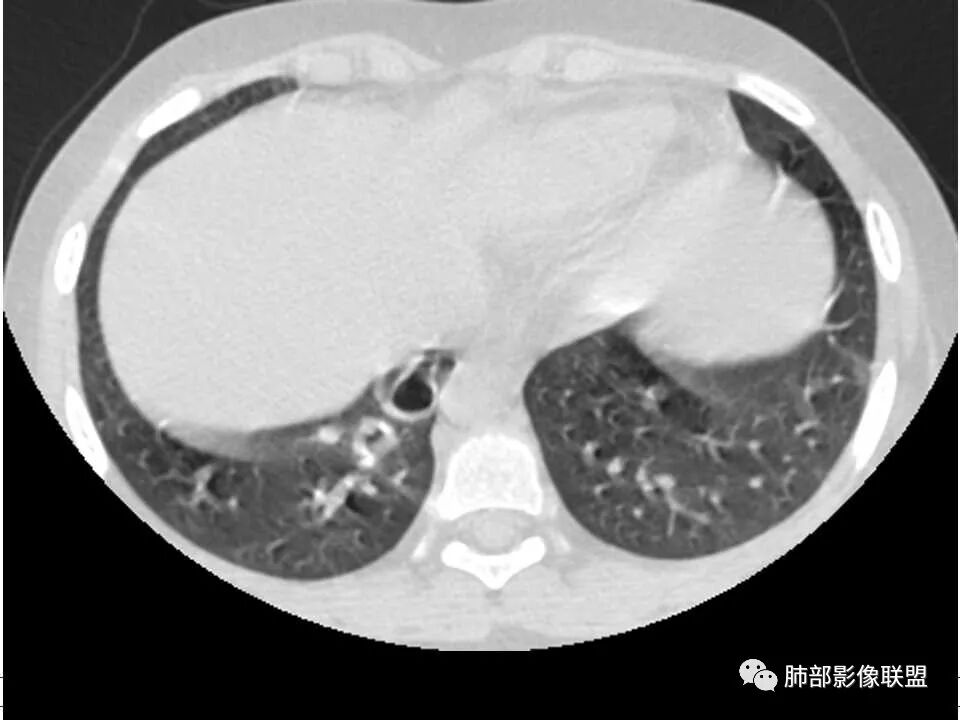

患者儿童,因右下肢疼痛伴肿胀14天就诊。病程中有发热及伴随症状。膝关节MRI提示右侧膝关节及右髌骨髁异常信号影,右膝髌上囊及关节腔内少量积液。胸部CT:双肺胸膜下多发结节影,部分结节空洞形成,且结节周围可见血管集束征。综合考虑血源性脓毒性肺栓塞、坏死性肺炎。右侧骨髓炎、血播性金葡菌肺炎,鉴别其他特殊感染及血管炎。

胸部ct:双肺多发空洞,结节,外带下叶为主,空洞内外光滑,有血管滋养征,综合病史及影像考虑脓毒性肺栓塞,结合病史,金葡可能性大。

2.双肺多发片影,随机分布,多空洞或囊腔,胸膜下多楔形影,气道未见受累等等符合脓毒血症影像学表现,尤其是金葡。